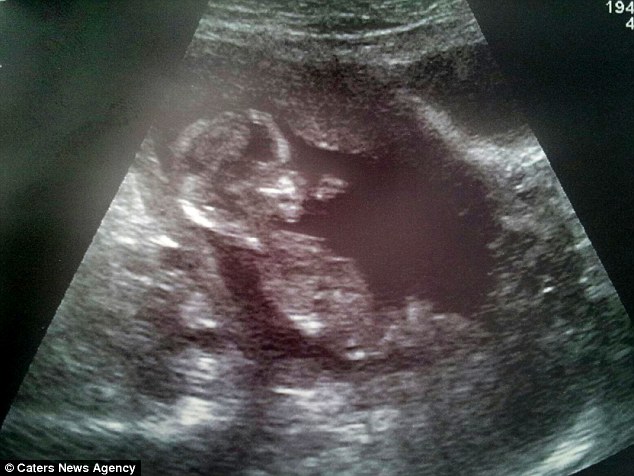

На 20 неделе беременности, Саре сделали узи.

Врач разглядел снимках девочку и он был 100% уверен в своем мнении.